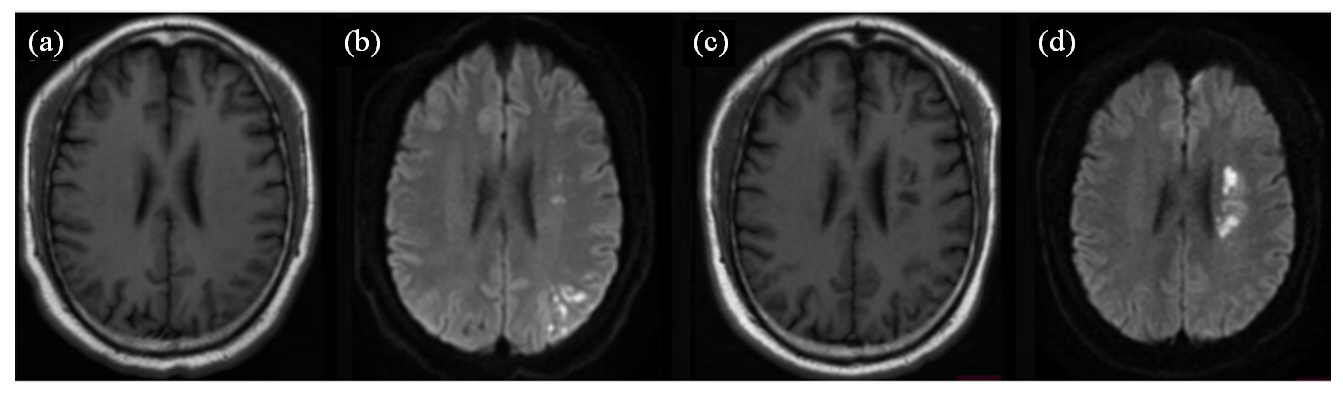

| 图1 一位多发急性脑梗塞复发患者磁共振轴位SE T1WI (a、c)、DWI (b、d)图像. 患者首次住院,行磁共振检查显示,左侧放射冠区和左侧顶叶区多个急性梗塞病灶,呈长T1信号(a),DWI弥散受限呈高信号(b);患者康复出院后6个月出现临床症状,行磁共振检查显示,左侧放射冠区多个急性梗塞病灶,呈长T1信号,左侧放射冠区见多个软化灶(c),DWI扩散受限呈高信号(d) |

| Fig. 1 Magnetic resonance axial SE T1WI (Fig. a, c) and DWI (Fig. b, d) of a patient with recurrent multiple acute cerebral infarcts. The patient was admitted to the hospital for the first time, and an MRI showed multiple acute infarction lesions in the left radiocaudate region and the left parietal lobe, with long T1 signals (Fig. a) and high DWI signals indicative of restricted diffusion (Fig. b). The patient developed clinical symptoms six months after discharge from rehabilitation, an MRI showed multiple acute infarction lesions in the left radiocaudate region with long T1 signals and multiple areas of infarction were also seen in the left radiocaudate region (Fig. c); diffusion-limited DWI with a high signal (Fig. d) |